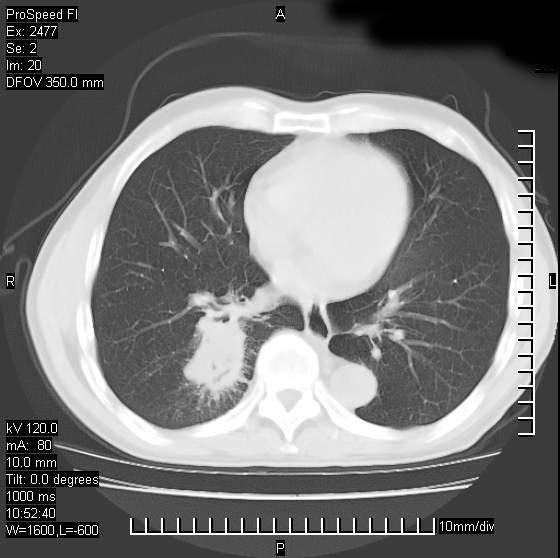

以下是引用天南地北在2007-10-9 14:29:00的发言:[br]1:右上肺结核[br]2:右肺下叶肿块:不支持肺癌,首先考虑炎性病变-肺脓疡可能性大[br]理由:1:临床病史支持,肺脓肿症状不明显应该是不规则服药造成。[br] 2:肿块边缘模糊,周围可见炎性渗出,长毛刺,内见支气管征,不过有点不规则。[br] 我感觉下肺癌这个诊断有点偏左,建议积极抗炎治疗后复查

以下是引用卜一在2007-10-9 15:55:00的发言:[br][br] [br] 1:右上肺结核[br]2:右肺下叶肿块:不支持肺癌,首先考虑炎性病变-肺脓疡可能性大[br]理由:1:临床病史支持,肺脓肿症状不明显应该是不规则服药造成。[br] 2:肿块边缘模糊,周围可见炎性渗出,长毛刺,内见空气支气管征,不过有点不规则。[br] 我感觉下肺癌这个诊断有点偏左,建议积极抗炎治疗后复查![br]支持! [br] [br] [br]

以下是引用wxy7406在2007-10-9 21:02:00的发言:[br]结合临床病史首先考虑感染性病变,但周围型肺癌不能除外,1.患者年龄偏大2.临床有咯血3.(也觉得是最重要的一点)病灶内有偏心性空洞。

以下是引用王仕学在2007-10-9 13:48:00的发言:[br]右下肺周围性肺癌可能性大,最好活检吧

以下是引用hhcckk在2007-10-9 15:18:00的发言:[br]右上肺病灶考虑结核,病灶多种形态并存(纤维化、增殖性病灶并存)[br]右下肺病灶比较难说,个人意见更趋向于“天南地北”的诊断----肺脓肿[br]1、病人有明显的寒战,高热,肿瘤病人很少出现[br]2、病灶周围的肺纹理走向柔和,没有肿瘤病灶常见的集束征[br]3、病灶边缘的毛刺较长,恶性肿瘤多为短毛刺[br]痰中血丝和病人的年龄是两个不利于良性肿块的因素,建议早点活检

以下是引用ydx_74在2007-10-9 15:53:00的发言:[br]右上肺结核,右下中心性肺癌可能大,肺门淋巴结肿大。